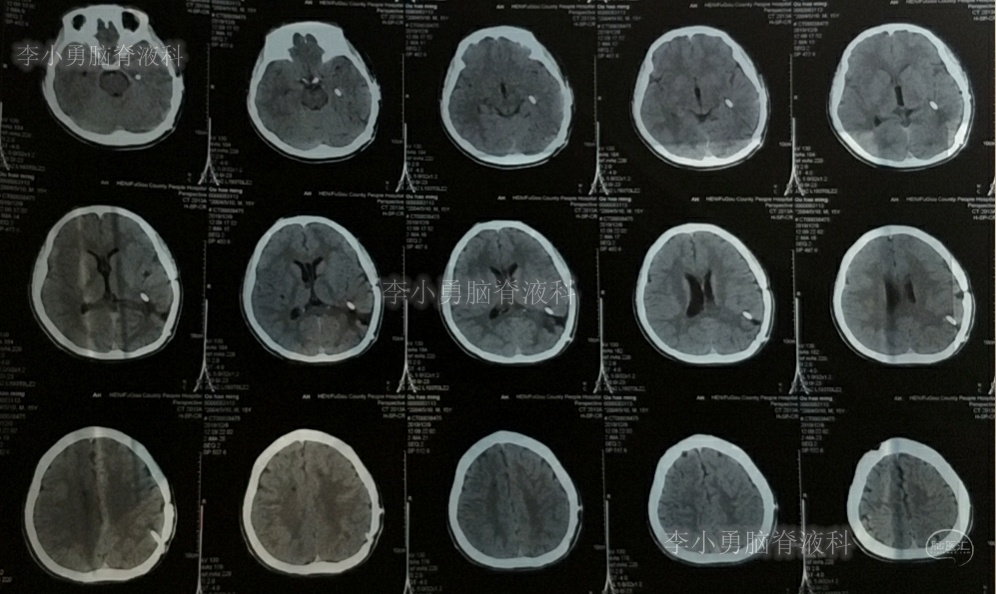

双侧脑室外引流5天后即2019年3月31日,脑脊液颜色由血性明显变淡,意识转清,肢体活动良好,给予复查头颅CT(图-3):脑室不大,残留少许积血。

图-3:2019年3月31日头颅CT:残留少许积血

双侧脑室外引流6天即2019年4月1日,给予常规拔除双侧脑室外引流管。但当晚再次出现剧烈头痛、烦躁及恶心,复查头颅CT(片子遗失)示脑室内再次出血,给予“对症处理”。

次日即2019年4月2日给予行腰椎穿刺术,引流出血性脑脊液;但腰椎穿刺术刚结束突然晕厥,再次复查头颅CT(图-4):脑室内出血量较前明显增多,四脑室及中央导水管铸形。

图-4:2019年4月2日头颅CT:脑室内积血明显增多